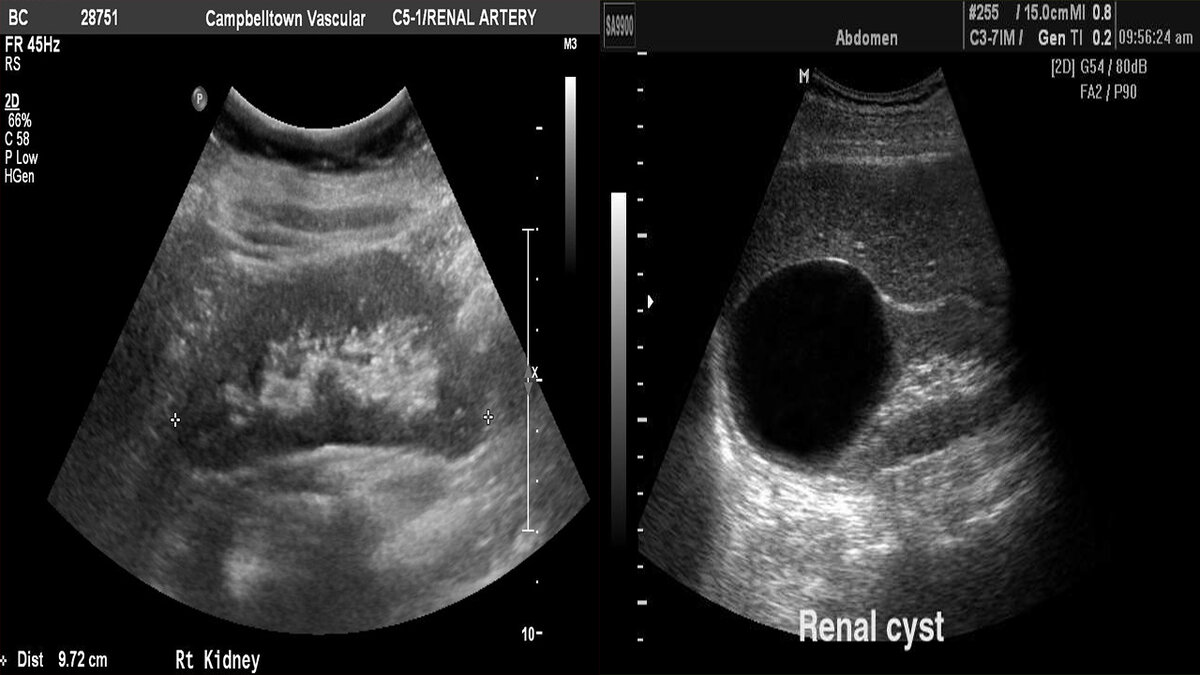

Выше я уже упомянул про УЗИ, это и есть основной метод исследования когда обнаруживаются кисты. При выполнении компьютерной томографии при диагностике каких-либо заболеваний также случайно находят кисты.

Киста - это полостное образование округлой или овальной формы с жидкостью, отграниченное стенкой из соединительной ткани. Кисты почек по частоте и многообразию форм находятся на первом месте среди кист забрюшинного пространства. Располагаются они непосредственно в тканевой структуре органа или под капсулой почки. Могут быть как единичными так и множественными, по статистике в правой почке несколько чаще чем в левой, и локализуются в различных сегментах. Кисты боле 15 см - крайне редкое явление, но такие тоже встречаются.

Почка при УЗ-исследовании, слева вариант нормы, справа - большая киста почки